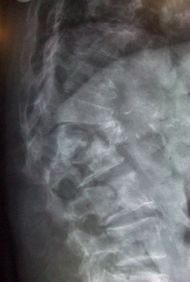

Multiple osteoporotic wedge fractures demonstrated on a lateral thoraco-lumbar

قد تبدأ الأعراض بصورة مفاجئة أو حادة; على هيئة آلام بالظهر, وعادة ما يكون ذلك نتيجة لحدوث كسر في إحدى فقرات العمود الفقري, لكن الأكثر شيوعا هو حدوث أعراض المرض بصورة تدريجية, وقد يكتشف الطبيب لدى الفحص الروتيني للمرضى المتقدمين في السن وجود كسور بسيطة بالفقرات, وقد لا تؤدي تلك الكسور إلى أية مضاعفات مثل الضغط على أعصاب الحبل الشوكي. وقد تقتصر شكوى المريض على الانحناء المتزايد لقامته نتيجة لانخفاض كثافة عظام الفقرات ونقص كتلتها.

- كسور العمود الفقري: 44%.

قد يؤدي نقص العظم, في الأفراد المصابين بتخلخل العظم, إلى حدوث كسور في العظام الفقرية مما يسبب, تدريجياً, انخماصاً في عظام العمود الفقري فيسبب ذلك قصراً في الطول وآلاماً مبرحة وتحدباً في الظــــهر (حدبة الأرملة النبيلة: Dowagerصs hump).